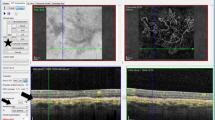

Because our purpose was to identify CNV, we included all types of CNV in the CNV population and all types of macular disease in others. In Fig. 1 is an example of imaging obtained for CSCR (no CNV) and in Fig. 2 an example of images presented for a patient with type 2 CNV.

Patient#5 presenting a typical case of type 2 CNV with subretinal hemorrhage complicating nAMD. Yellow arrow fluorescein leakage expanding over the course of the angiography. White arrow subretinal hemorrhage, masking effect. White star dome-shaped hyperreflective subretinal area on SD-OCT imaging corresponding subretinal hemorrhage. Yellow star exudative signs on SD-OCT: intraretinal cyst, retina serous detachment, subretinal hyperreflective exudation, thickened retina

Images were shown in three stages. The first stage consisted of presentation of OCT-A images (four image frames per patient: superficial plexiform vascular layer, deep plexiform vascular layer, outer retinal layer and choriocapillaris; Fig. 3 shows examples of images of choriocapillaris or outerretinal layer slabs to be interpreted by study participants). 1 week later, FA images were presented [3–4 frames: very early phase, early phase, late phase and very late phase (when available) per case].

Highlight of the most informative layer in OCT-A imaging for two of the cases. a Patient #8 presenting a typical case of type 1 CNV in AMD. White star: larger trunk. Yelllow star: branching pattern and anastomosis. b Patient #13 presenting vascular dilatation. Yellow arrows: perimacular vascular dilatation. White arrow: perifoveal microvasculature rupture